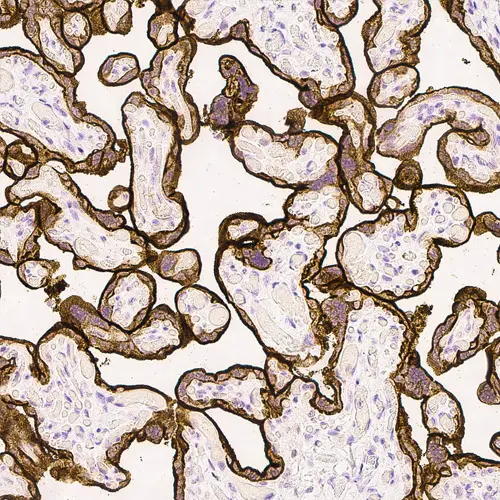

Hodgkin’s lymphoma: in situ hybridization for Epstein-Barr virus (EBV) encoded mRNA using EBER Probe, Anti-Fluorescein Antibody and BOND Polymer Refine Detection.

Background Epstein-Barr Virus (EBV) is a member of the Gamma Herpes Virus family. EBV can establish both lytic infection as well as latent infection.

Epstein Barr Virus encoded RNA is abundantly expressed in latent EBV infection and ISH is considered a sensitive method for the detection of latent EBV infection.

Latent EBV infection is associated with several conditions including: Hodgkin's Lymphoma, B cell Non Hodgkin's Lymphoma, nasopharyngeal carcinoma, lymphoproliferative disorders and lymphoma in the immunosuppressed, including transplant and AIDS patients, gastric cancer and some T cell lymphomas.